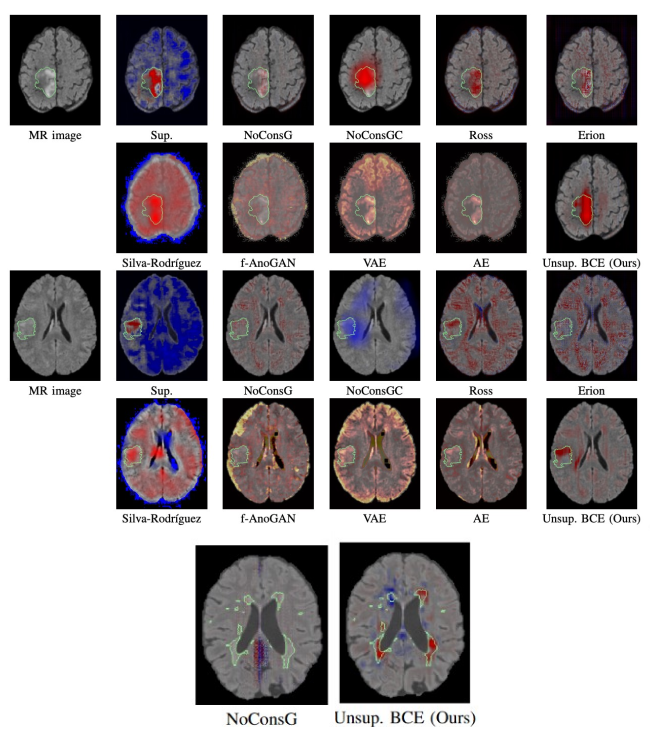

Cartes d'attributions du classifieur entrainé de manière classique (NoConsG) ou avec notre contrainte faiblement supervisée (Unsup BCE (ours)) sur des images de sujets ou avec une tumeur cérébrale avec l’illustration de l’ensemble des méthodes (en haut ; image IRM, supervisée, avec huit autres méthodes, NoConsG, NoConsGC, Ross, Erion, Silva-Rodriguez, f-AnoGAN, VAE, AE) ou atteints de sclérose en plaques illustrés ici avec deux méthodes (en bas). L'annotation manuelle est dessinée en vert, les zones rouges font pencher la décision du réseau vers la classe "pathologie", les zones bleues, vers la classe "sain". On peut voir que notre contrainte va induire une concentration du gradient beaucoup plus forte sur les lésions ou les tumeurs même si aucune information sur les lésions n'a été fournie pendant l'apprentissage.